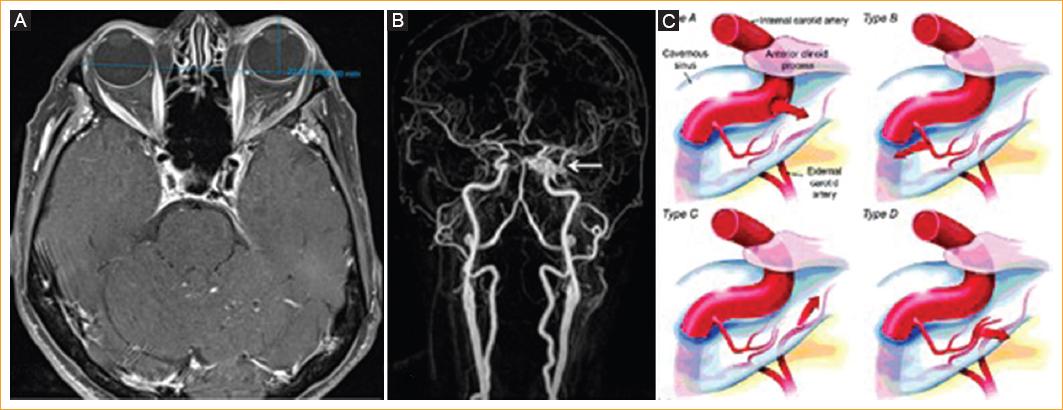

Se realiza una resonancia magnética y en la secuencia T1 axial contrastada con saturación grasa se evidencia un engrosamiento difuso de los músculos extraoculares, principalmente del recto medial y respetando el tendón y la inserción musculares, además de proptosis ocular izquierda de 22 mm (Fig. 3 A). La primera lectura por neurorradiología sugiere una oftalmopatía distiroidea como primer diagnóstico. Debido a la discrepancia clinicorradiológica, con hipofunción del recto lateral al examen físico y engrosamiento principalmente del recto medial en la resonancia, además de no mejorar con esteroides, se solicita una nueva lectura por otro neurorradiólogo y se encuentran signos de fístula carotidocavernosa en las secuencias de angiorresonancia dados por una asimetría vascular en el seno cavernoso izquierdo, en comparación con el derecho, y una dilatación de la vena oftálmica superior izquierda (Fig. 3 B).

Figura 3 A: adquisición axial de resonancia magnética contrastada en secuencia T1 con saturación grasa. Se observa engrosamiento de los músculos extraoculares, principalmente del recto medial, y proptosis ocular izquierda de 22 mm. B: angiorresonancia cerebral que muestra asimetría en el seno cavernoso izquierdo (flecha) y dilatación de la vena oftálmica superior izquierda. C: clasificación de Barrow de las fístulas carotidocavernosas (tomada de Ellis, et al.2).

Tras estos hallazgos se realiza una angiografía cerebral para confirmar el diagnóstico (Fig. 4 A), en la que se demuestra una fístula carotidocavernosa de bajo flujo que, según la clasificación de Barrow3 (Fig. 3 C), es indirecta tipo B nutrida por ramas durales del tronco meningohipofisiario de la carótida interna izquierda (Fig. 4 A). Se procede entonces a realizar una embolización con coils por vía endovenosa, a través del seno petroso inferior, hasta llegar al seno cavernoso (Fig. 4 B). El control angiográfico final (Fig. 4 C) muestra la completa oclusión de la fístula por los coils.